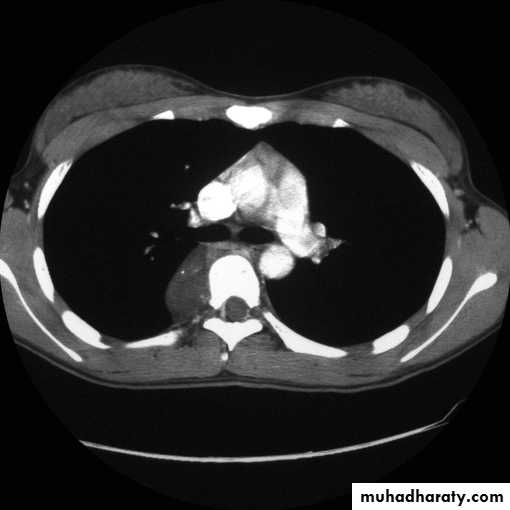

2-CT scan: indications:

• Assessment of trauma and emergency conditions.• assessment of masses( primary & secondary).

• Diagnosis Of interstitial disease.(HRCT...High resolution CT )

• guided procedures.

• CT angiography in suspected pulmonary embolism.

mediastinal window bone window lung window